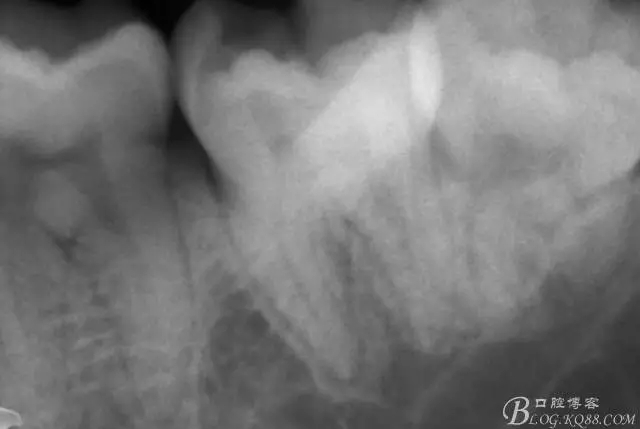

一周后復診,37叩(—)。去除暫封物,沖洗,試主尖拍片。

X線示牙膠尖到達工作長度,故行AH-PLUSH糊劑配合卡瓦熱牙膠機運用連續(xù)波充法根充,暫封拍根尖片。